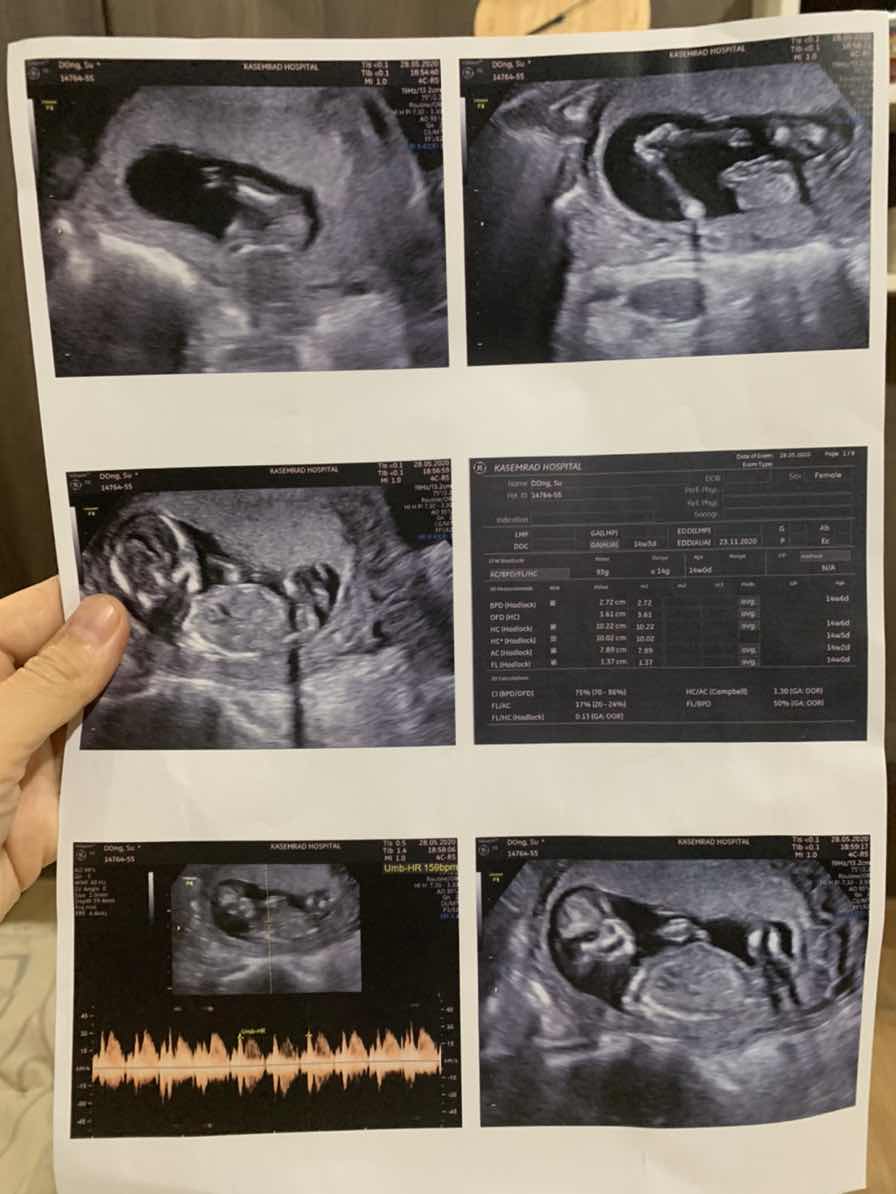

มีแม่ๆบ้านไหนกำหนดคลอดพฤศจิกายนกันบ้างคะ . เอารูปอัลตร้าซาวมาอวดกันหน่อยจ้า ของน้อง15วีคแล้ววว ?

ซาวด์ตอน15w กำหนดคลอด 22 พย จ้า